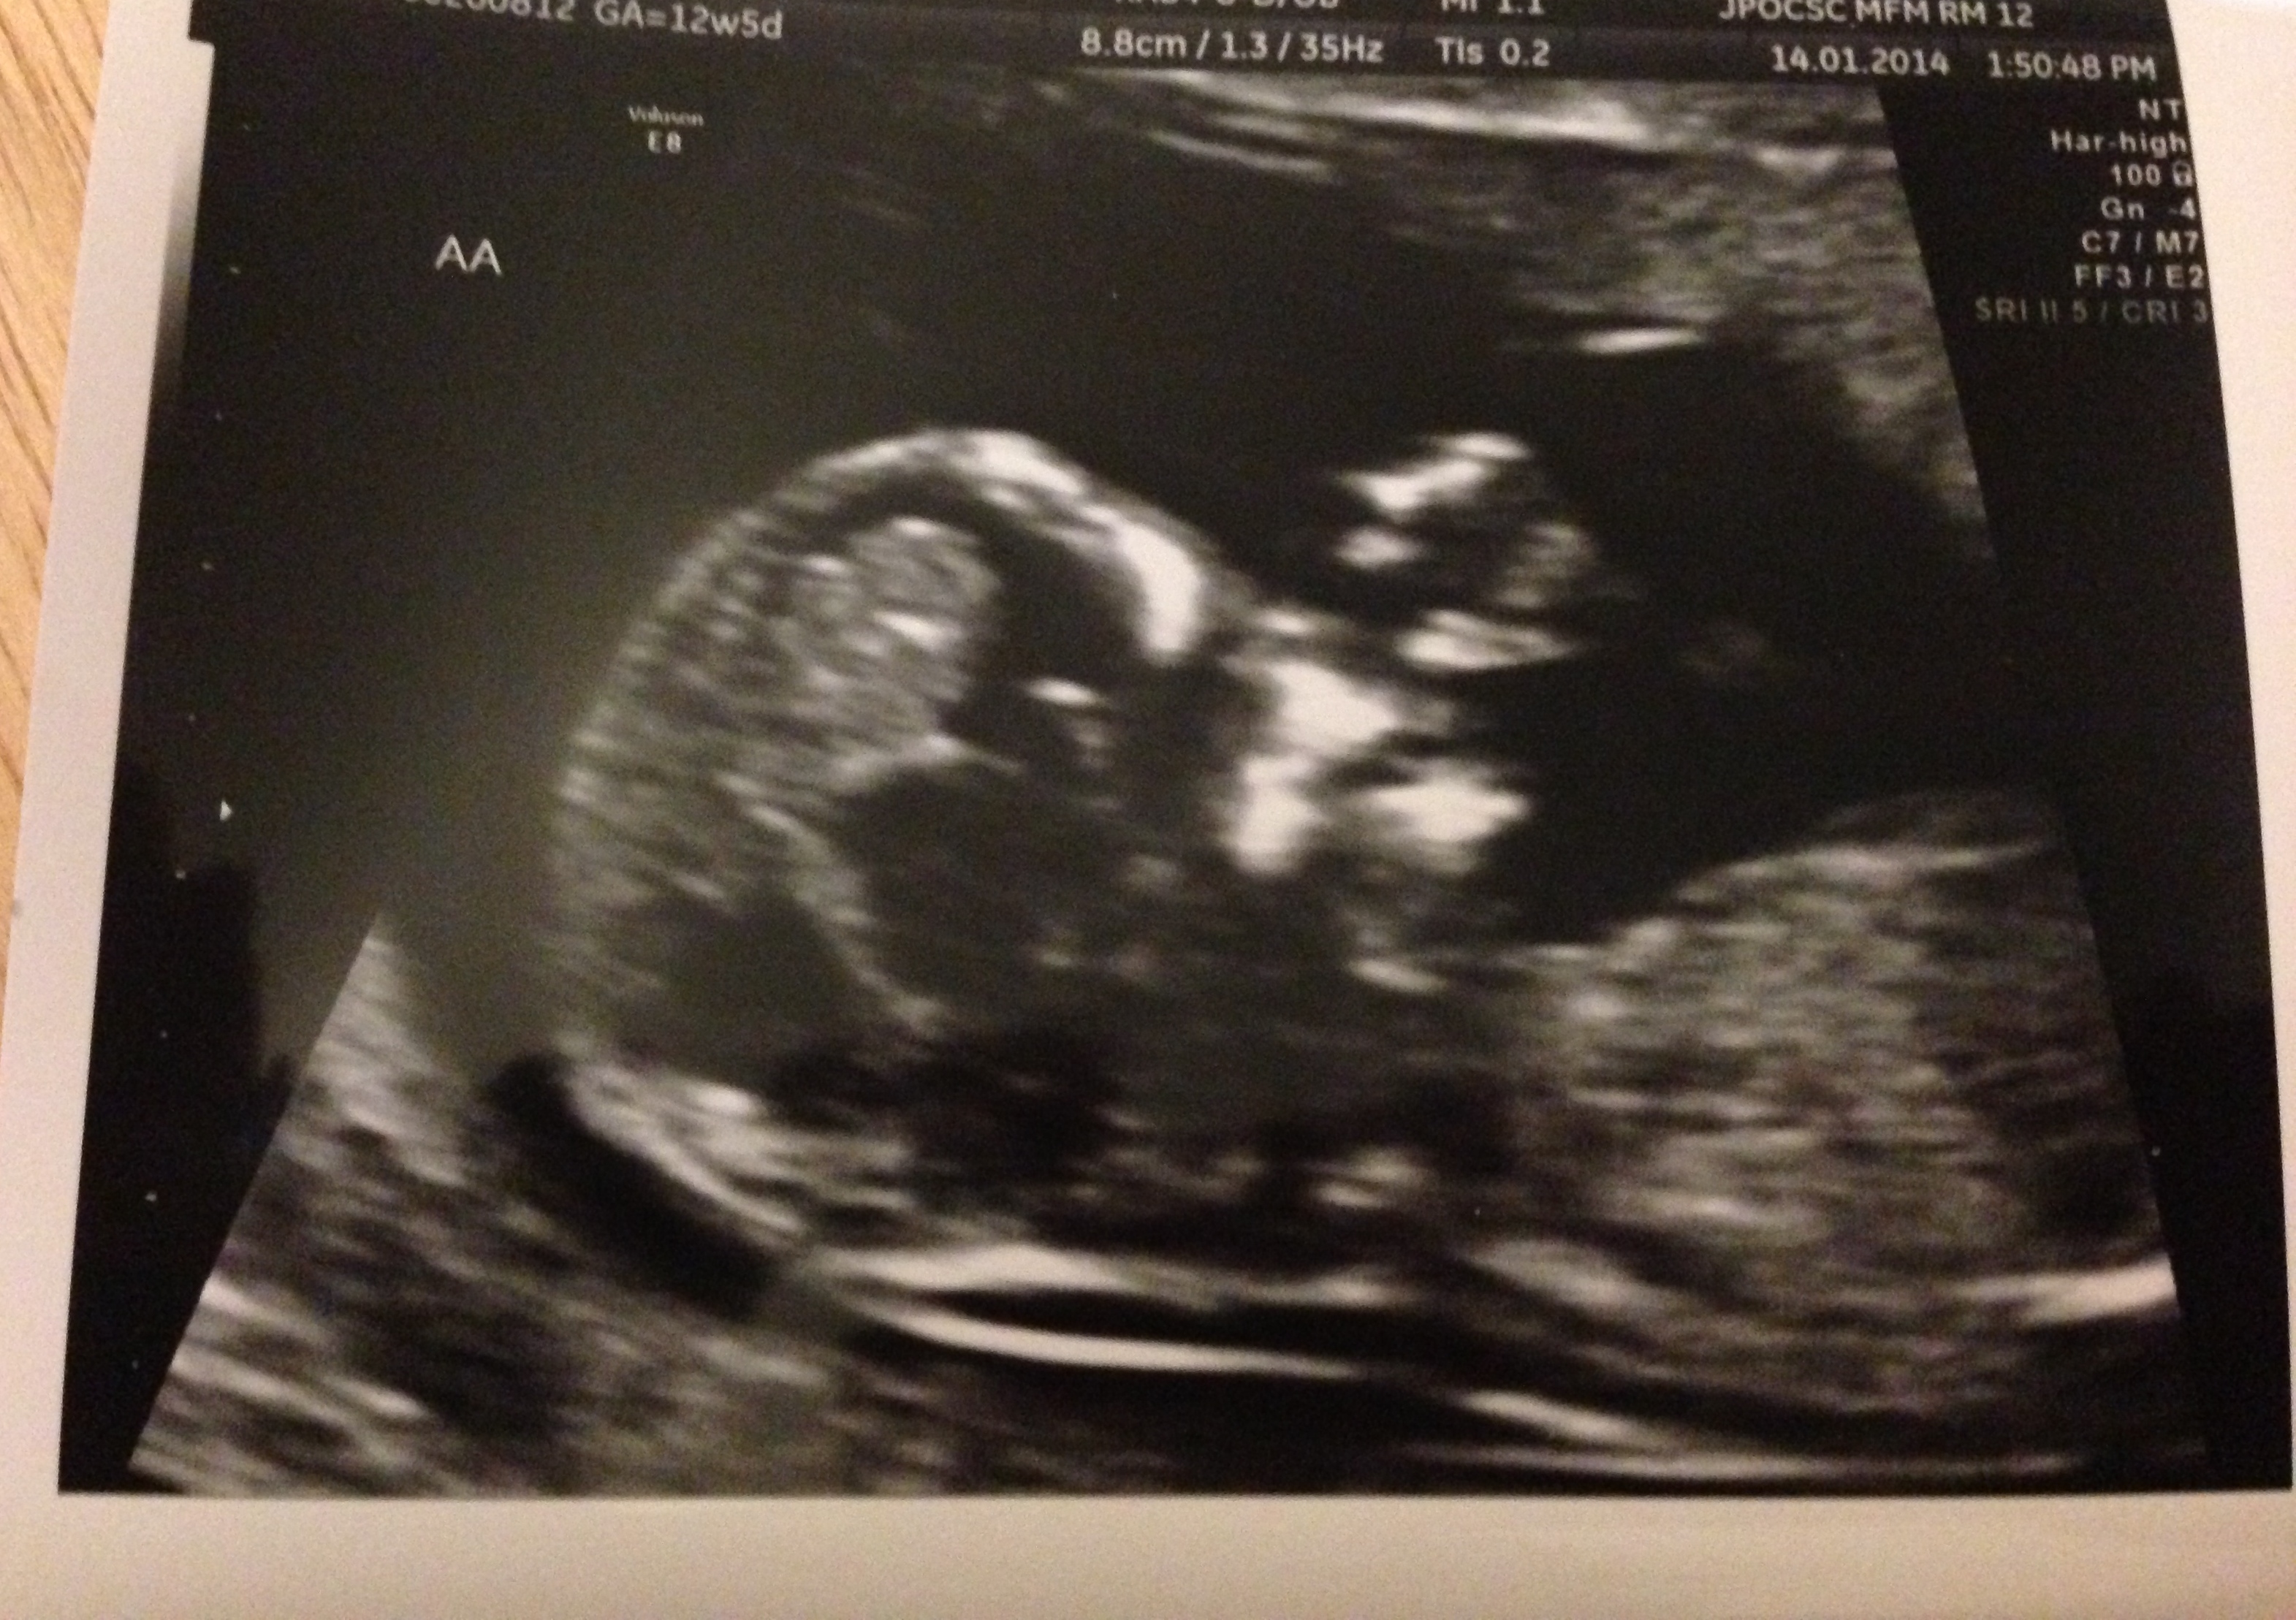

Today I met with my MFM for the first time and ended up getting an NT scan out of it! Both babies looked great and they were wiggling around a bunch, was very cute.  He did tell me b/c they're di/di I don't need to keep seeing him in conjunction with my OB. I'm still high risk, but the lowest of the high risk I guess. I was a bit upset at first, but I assume he knows what he's doing. I also get to go for an early GD screening this week, so I have that to look forward to.

Anyways, just wanted to share. I'd been looking forward to this appointment since I got it. And here's pictures of the little babies (and yes, that's A's hand at his/her mouth). And thanks for all the support the other day in regards to the MFM questions. It was so helpful!